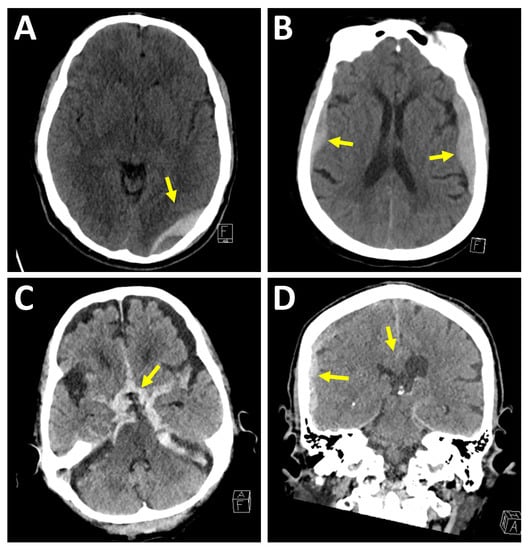

Figure 1.

Extra-axial hemorrhage patterns. (A) Epidural hematoma. Thirty-three-year-old man was brought in by ambulance after a motor vehicle accident. Axial image demonstrates a biconvex shaped extra-axial fluid collection superficial to the left occipital lobe with hyperdense and hypodense components. Adjacent left temporal bone fracture not seen on this axial image. (B) Bilateral subdural hematomas. Seventy-three-year-old woman presented after a fall out of bed with dizziness. Axial image demonstrates bilateral crescentic shaped fluid collections, which were found to cross the coronal sutures. (C) Massive subarachnoid hemorrhage. Ninety-seven-year-old man on anticoagulation fell while walking. Axial image demonstrates a subarachnoid hemorrhage within the basal cisterns. Patient expired five days later due to cardiorespiratory failure. (D) Subdural hematoma with developing subfalcine herniation. Sixty-nine-year-old man on anticoagulation fell and struck his head. Coronal image demonstrates subdural hematoma along the right cerebral convexity with mass effect on adjacent lateral ventricle, midline shift, and subfalcine herniation.

In a subdural hematoma, the hematoma is located between the dura mater and the arachnoid membrane; therefore, subdural hematomas can travel across calvarial sutures and along the falx cerebri and tentorium cerebelli. Subdural hematomas are commonly caused by shearing of bridging veins, which can be due to the mobile, rotating brain with respect to the fixed dura mater []. Subdural hematomas generally involve a higher degree of underlying brain injury as compared to epidural hematomas. Underlying cerebral edema, mass effect, or midline shift may contribute to the feared complication of elevated ICP and cerebral herniation. Also, in contrast to epidural hematomas, which typically present in the acute phase, subdural hematomas commonly present at varying ages of hemorrhage, see Figure 1.

In subarachnoid hemorrhages, the hemorrhage is located within the subarachnoid space and can be seen in the sulci between the cortical gyri, the fissures between the cerebellar folia and the cisterns such as the basal cisterns or the perimesencephalic cistern. Once hemorrhage enters the subarachnoid space, it can undergo a variable amount of dilution by the cerebrospinal fluid. In addition to trauma, an important and common cause of subarachnoid hemorrhage is aneurysmal hemorrhage [], see Figure 1.

In an epidural hematoma, the hematoma is located between the dura mater and the calvarium. Clinically, epidural hematomas can be associated with a lucid interval followed by clinical deterioration once a critical level of intracranial pressure (ICP) is reached []. Epidural hematomas are typically biconvex shaped, commonly associated with skull fractures and commonly arise from arterial bleeding, such as the middle meningeal artery in children. Since the middle meningeal artery enters the skull through the foramen spinosum at the floor of the middle cranial fossa, the neuroradiologist must look carefully at the floor of the middle cranial fossa on the coronal images for an epidural hematoma. Epidural hematomas can also be caused by venous injuries such as at the dural venous sinuses. On rare circumstances, an epidural hematoma can decompress outward through a skull fracture into the scalp. Epidural hematomas are most commonly encountered in the acute phase, see Figure 1.